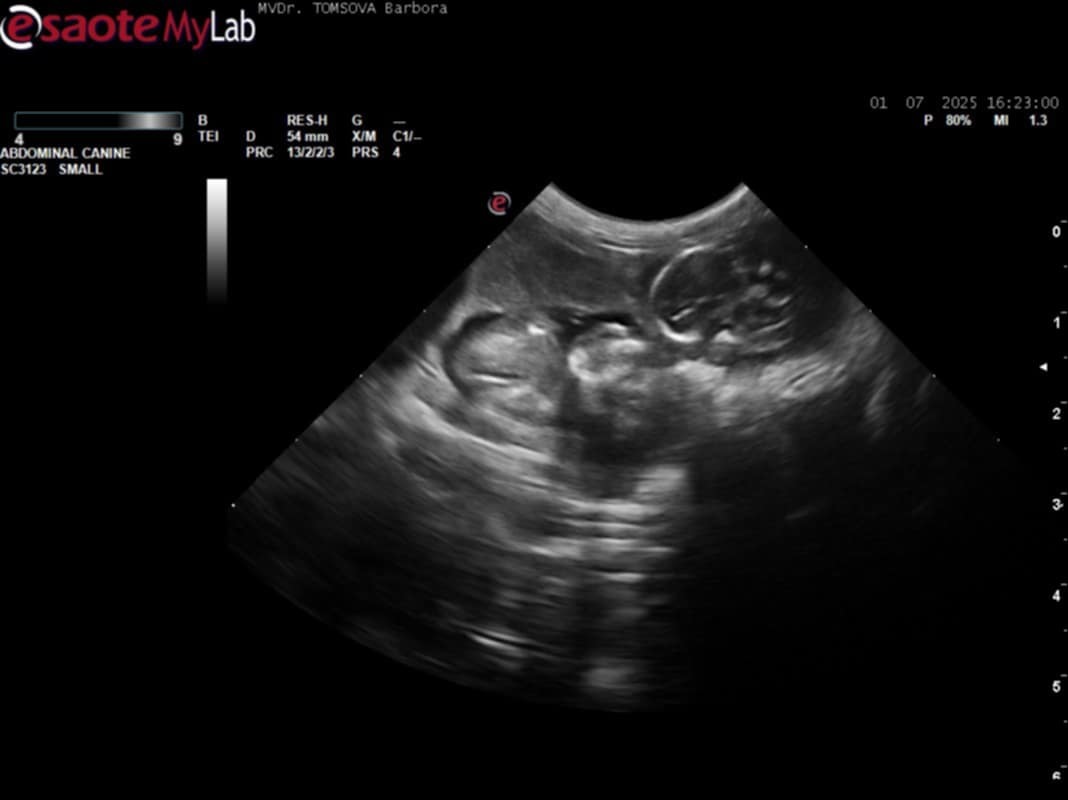

• 1.7.2025 potvrzena březost a 2.8.2025 porodila 5 zdravých mláďat